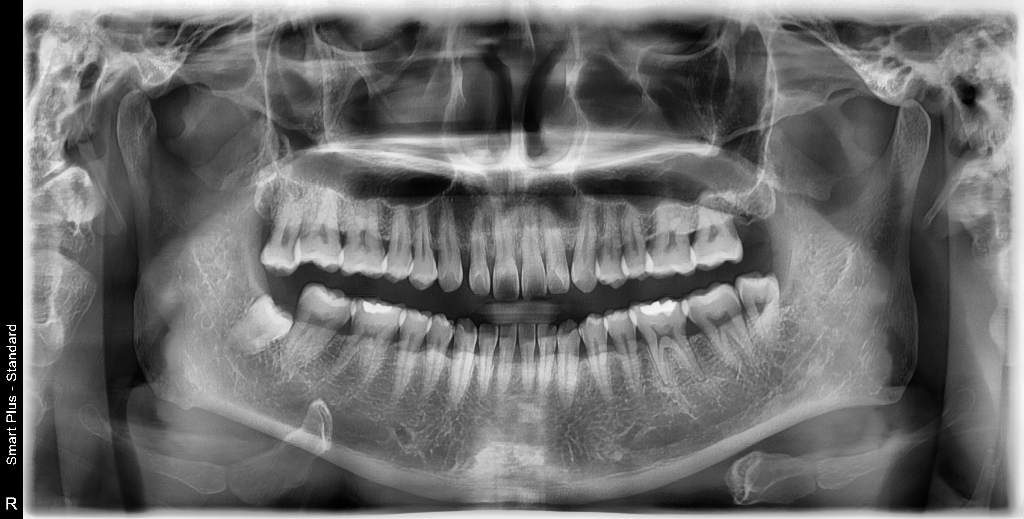

다른쪽 미세한충치도 병원 전부 다 그냥 써도 될거같다고 하는데 이곳만 인레이를 이야기하네요. 엑스레이 사진 올려봅니다. 엑스레이는 크라운씌우기 전 엑스레이입니다.

엑스레이 사진상으로는 신경치료를 하고 크라운 치료를 한 치아가 보이진 않습니다. 하지만 신경치료까지 하고도 증상이 사라지지 않앗다면 올려 놓은 치아상태라면 발치 즉시 식립을 하셔도 될것같습니다.